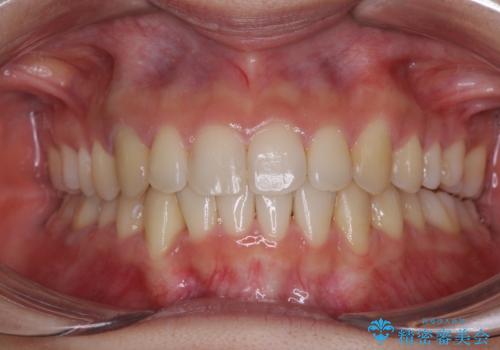

- 前歯のデコボコと若干口元が突出していることを気にして来院された患者様です。

全体的に軽微な叢生が認められ、口元もやや前方に突出していたため、インビザラインでのIPR(歯と歯の間を削る)と歯列全体の後方移動によって歯並びを整えることとしました。

上下ともに歯列の幅が狭かったため、側方に拡大することで前歯のデコボコや突出感を解消するためのスペースを獲得することができました。

歯並びが改善したことはもちろん、咬み合わせの改善まで実感することができ、患者様には大変満足していただけました。